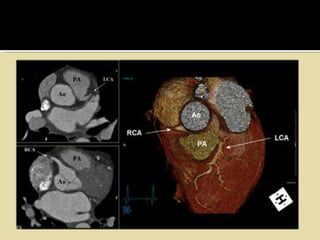

   Origin of the left coronary artery from the right sinus of Valsalva with the

artery passing between the aorta and pulmonary artery.

   Only a single coronary ostium in the right sinus of Valsalva with the left

coronary artery arising from the proximal right coronary artery

   Origin of the right coronary artery from the left sinus of Valsalva.

artery passing dorsal to the aorta rather than between the aorta and

pulmonary artery.

• #23 Other congenital anomalies that are less compatible with life are bridging of the coronary arteries, Dissecting coronary aneurysm and coronary artery spasm. Bridging of coronary arteries – This refers to the anomalous pathway of the epicardial arteries where the artery runs an intramural couse. Therefore, on contraction of myocardium, the artery gets occluded, leading to ischemia and thereby may be a cause of sudden death. Dissecting coronary aneurysm – may be primary or secondary to extension of the aortic root dissection. The extension of the aortic root dissection may be spontaneous or due to trauma. Seen more commonly in peri-partal females. Coronary artery spasm – In this, the coronary artery undergoes spasms which cause significant constriction and decrease in blood supply leading to ischemia. Angina associated with acute MI-like symptoms are the primary complaints. However, on autopsy, infarct is not seen and neither is there any significant atherosclerosis. This is seen in Printzmetal’s angina and unstable angina.

• #24 The illustration in the left upper corner is the most common and clinically significant anomaly. There is an anomalous origin of the LCA from the right sinus of Valsalva and the LCA courses between the aorta and pulmonary artery. This interarterial course can lead to compression of the LCA (yellow arrows) resulting in myocardial ischemia. The other anomalies shown do not produce hemodynamic instabilities.

• #25 Interarterial LCA On the left images of a patient with an anomalous origin of the LCA from the right sinus of Valsalva and coursing between the aorta and pulmonary artery. Sudden death is frequently observed in these patients.